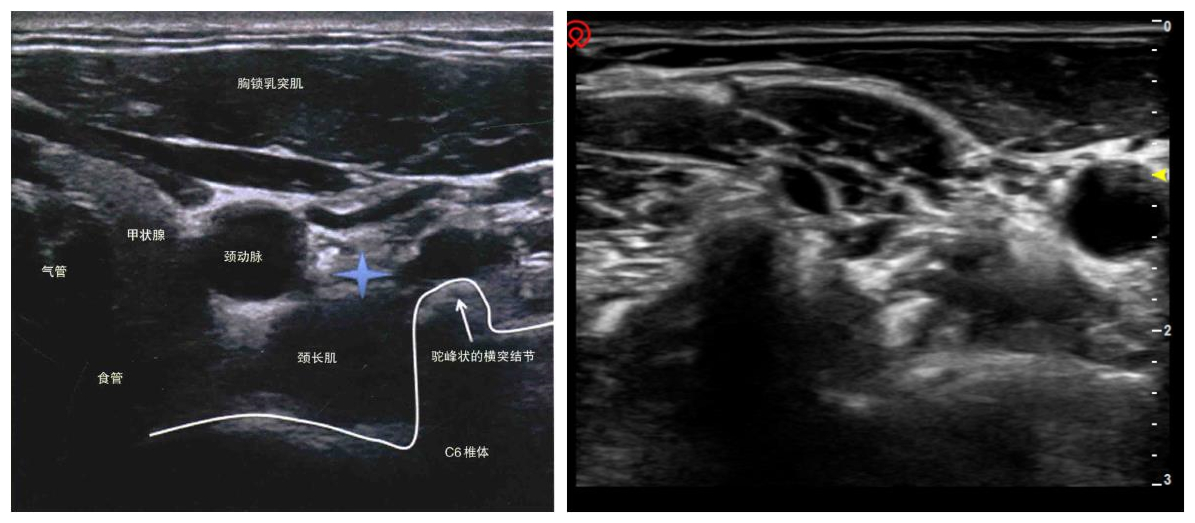

星状神经节是位于第七颈椎横突前缘的颈部交感神经节。通过阻滞星状神经节,可解除星状神经节的过度紧张及功能亢进状态,使头、颈、上肢、心脏等血管扩张,明显改善心、脑血流量,增强机体的抗病功能及抗炎作用,调节内分泌系统,使全身自主神经系统稳定化。该方法在日本是最广泛地应用于临床的疼痛治疗方法,占疼痛科治疗工作的60%~84%,在国内的疼痛治疗中使用率约占50%左右。鉴于该治疗方法广泛的适应性和在国内外应用中取得的良好疗效,我院疼痛门诊结合自身特点,将该治疗方法引入到疼痛疾病的治疗中,目前已为20余名患者解除病痛。通过随访发现,与仅用传统治疗方法进行治疗的患者相比,配合星状神经节阻滞治疗可明显缓解患者的不适症状,缩短患者的住院治疗时间。